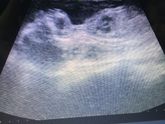

По мес 21 неделя ровно , по УЗИ 20,3..

на первом скрининге в другой больнице ставили срок ровно по месячным .. запуталась уже ???♀️

Сегодня наконец-то сходили на УЗИ ?

Все хорошо, лежим пока поперёк, весим 360 гр. ?

Папе показали всё особенно попку ?

И долгожданное «У вас девочка »

Рады до безумия ???

Теперь могу сказать с уверенностью что у меня там Варвара Александровна ❤️❤️❤️❤️